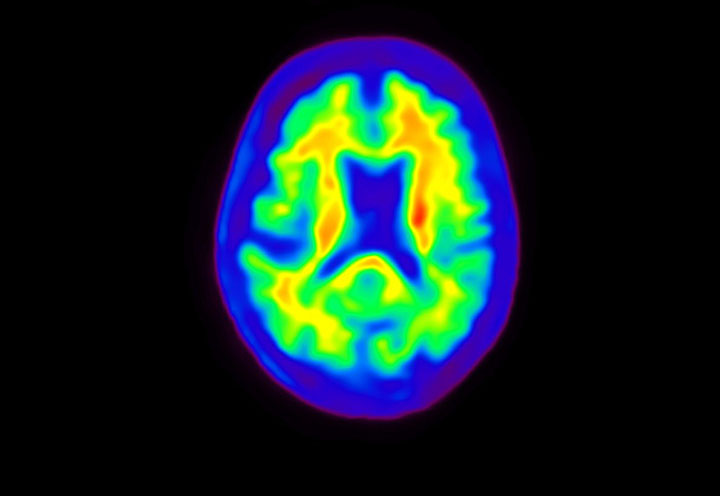

Head / Case4 : Amyloid

Axial

Courtesy : Kindai University Hospital

- Imaging protocol

- Injected dose: 3.21 MBq/kg, 18F-Flutemetamol

- Uptake time: 100 minutes

- Scan time: 20 minutes